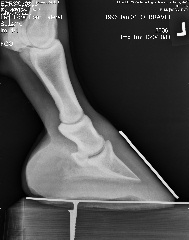

Posted on Saturday, Dec 23, 2006 - 5:11 pm: Right front Left front

| Member: Sunny66 |

Posted on Saturday, Dec 23, 2006 - 5:25 pm: Vet saw right fore, so he blocked right fore heel and he was "sounder" -- still off on left fore after block.Did the navicular series (won't post all of those unless you want to see them) xray guy said (after some prodding from me for info since the vet had left 45 minutes before for an emergency) he didn't see anything that popped out to him as awful. Coffin joint looked squished on both front feet on the OUTSIDE... I think THIS is his problem. Waiting OH so patiently for the vet to review, he promised he'd call me today. |

Posted on Saturday, Dec 23, 2006 - 5:49 pm: The xrays were taken with shoes off... so he's out of alignment with shoes off... so what would it take to get him in line? Anyone want to guess? I've emailed the farrier consultant the xrays... so we'll see what he says too. |

Posted on Saturday, Dec 23, 2006 - 11:30 pm: I'm sorry Aileen! Sometimes it takes pasture rest! Keep at those feet and don't let him get too fat.Hank had a year off while I got his hooves better and he was nqr for that long. Lucky for me I had Muddy Sam for a back up horse, but Hank is my favorite to ride. It was worth the wait and as you know he is now sound and barefoot. There is hope The only thing I see in the X-ray is his toe looks a little long yet, but it all takes time. Good Luck and keep us updated please. |

Posted on Sunday, Dec 24, 2006 - 12:38 am: Aileen, boy, looking at your x-rays compared to Levi,(bute or banamine) and I think Levi looks awful. He is still not really sound walking or trotting, but seems happy, and not really working, so I am hoping we can keep working on getting him straight. Good luck with your boy.suz |